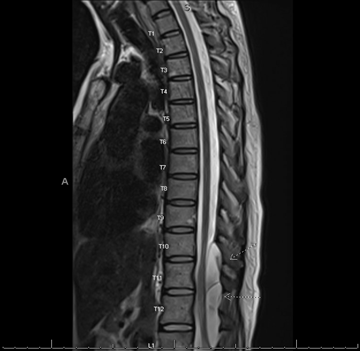

The patient is a 42-year-old female with no pertinent past medical history who presents to neurosurgery spine clinic citing chronic back pain and muscle spasms after failure of conservative treatment including physical therapy, epidural steroid injections, and medications. The patient underwent preoperative imaging using CT and MRI and was diagnosed with a 7.1 cm extradural arachnoid cyst at T11 to L1; Preoperative MRI displayed in figures 1-3 below. This extradural arachnoid cyst was causing compression of the cord and resulting in severe and worsening thoracic back pain and bilateral lower-extremity symptoms including pain, numbness, and loss of balance. The patient was positioned in a lateral decubitus position, lumbar region prepped with chlorhexidine then draped in usual sterile fashion. Lumbar drain was placed, clear CSF obtained, 0.2cc fluorescein in 10cc sterile saline was injected then the lumbar drain was secured with Ioban.

Figure 1: Sagittal T2 weighted MRI without contrast done preoperatively demonstrating a large SEAC spanning T11 to L1